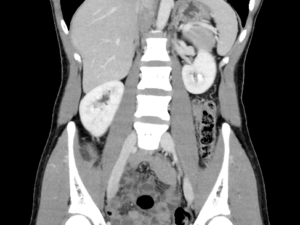

CT検査

当院では、Canon製Aquilion Prime SP 80列を使用しています。短時間で広範囲の撮影ができる他に、撮影したデータを元に任意の角度に合わせた断面像を生成したり、骨や臓器を3次元的に表示して観察することができます。また当院では3D医用画像処理ワークステーション(ZIO・VINCENT)を導入しており、より詳細な3次元画像の作成を行っています。